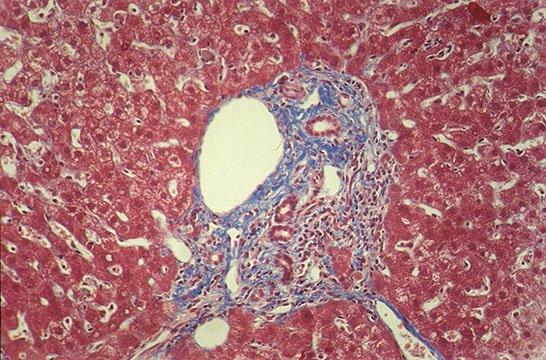

Fibrous changes

Fig 114 - Fibrous changes: Fibrous expansion of all portal

fields with occasional portal-portal Bridging. Score=3